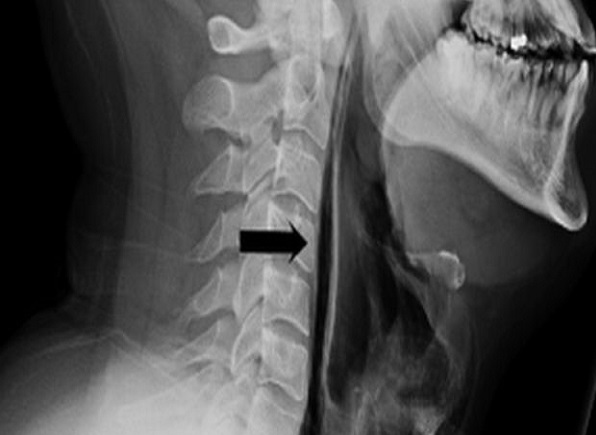

Röntgen çekildikten sonra, “cerrahi amfizem” adı verilen ve havanın kişinin vücudundaki en derin dokunun altında sıkışıp kalabildiği bir rahatsızlığı olduğu anlaşıldı. Hava, adamın boynundaki omurların yanı sıra göğsü ile akciğerleri arasındaki boşlukta sıkışıp kalmıştı.

Doktorlar tarafından yapılan kontroller neticesinde adamın ameliyata ihtiyacı olmadığı ve yırtığın, “soluk borusunda oluşan basınçtan kaynaklandığı” belirlendi.